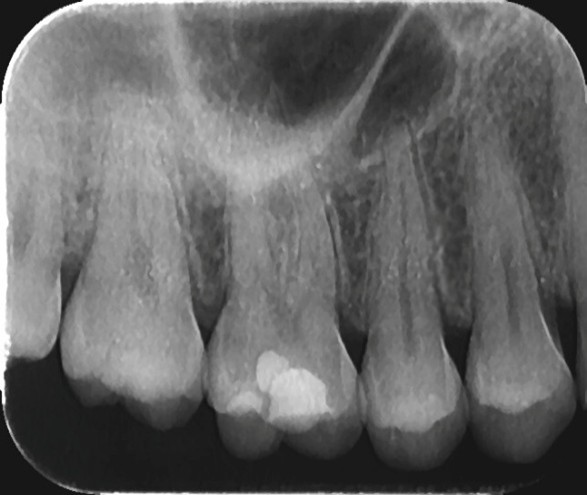

Retroalveolarni snimak zuba je nešto što se često zahteva u toku lečenja zuba i često je i obavezno...